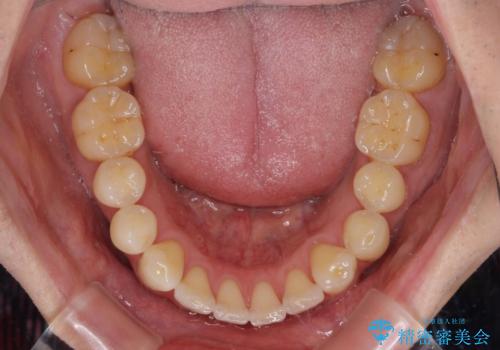

- 以前矯正治療を行ったものの、思い通りの仕上がりではなく、更には後戻りが気になってきたとのことで来院された患者様です。

上顎右側の第一小臼歯が動きにくい歯であり、以前矯正治療を行った際に傾斜した位置のまま終了したことと、それに伴い後戻りで歯列が波打っているようになっていることを大変気にしていらっしゃいました。

咬合平面改善のため、アンカースクリューを多用し、ワイヤー装置にて矯正治療を行うこととしました。